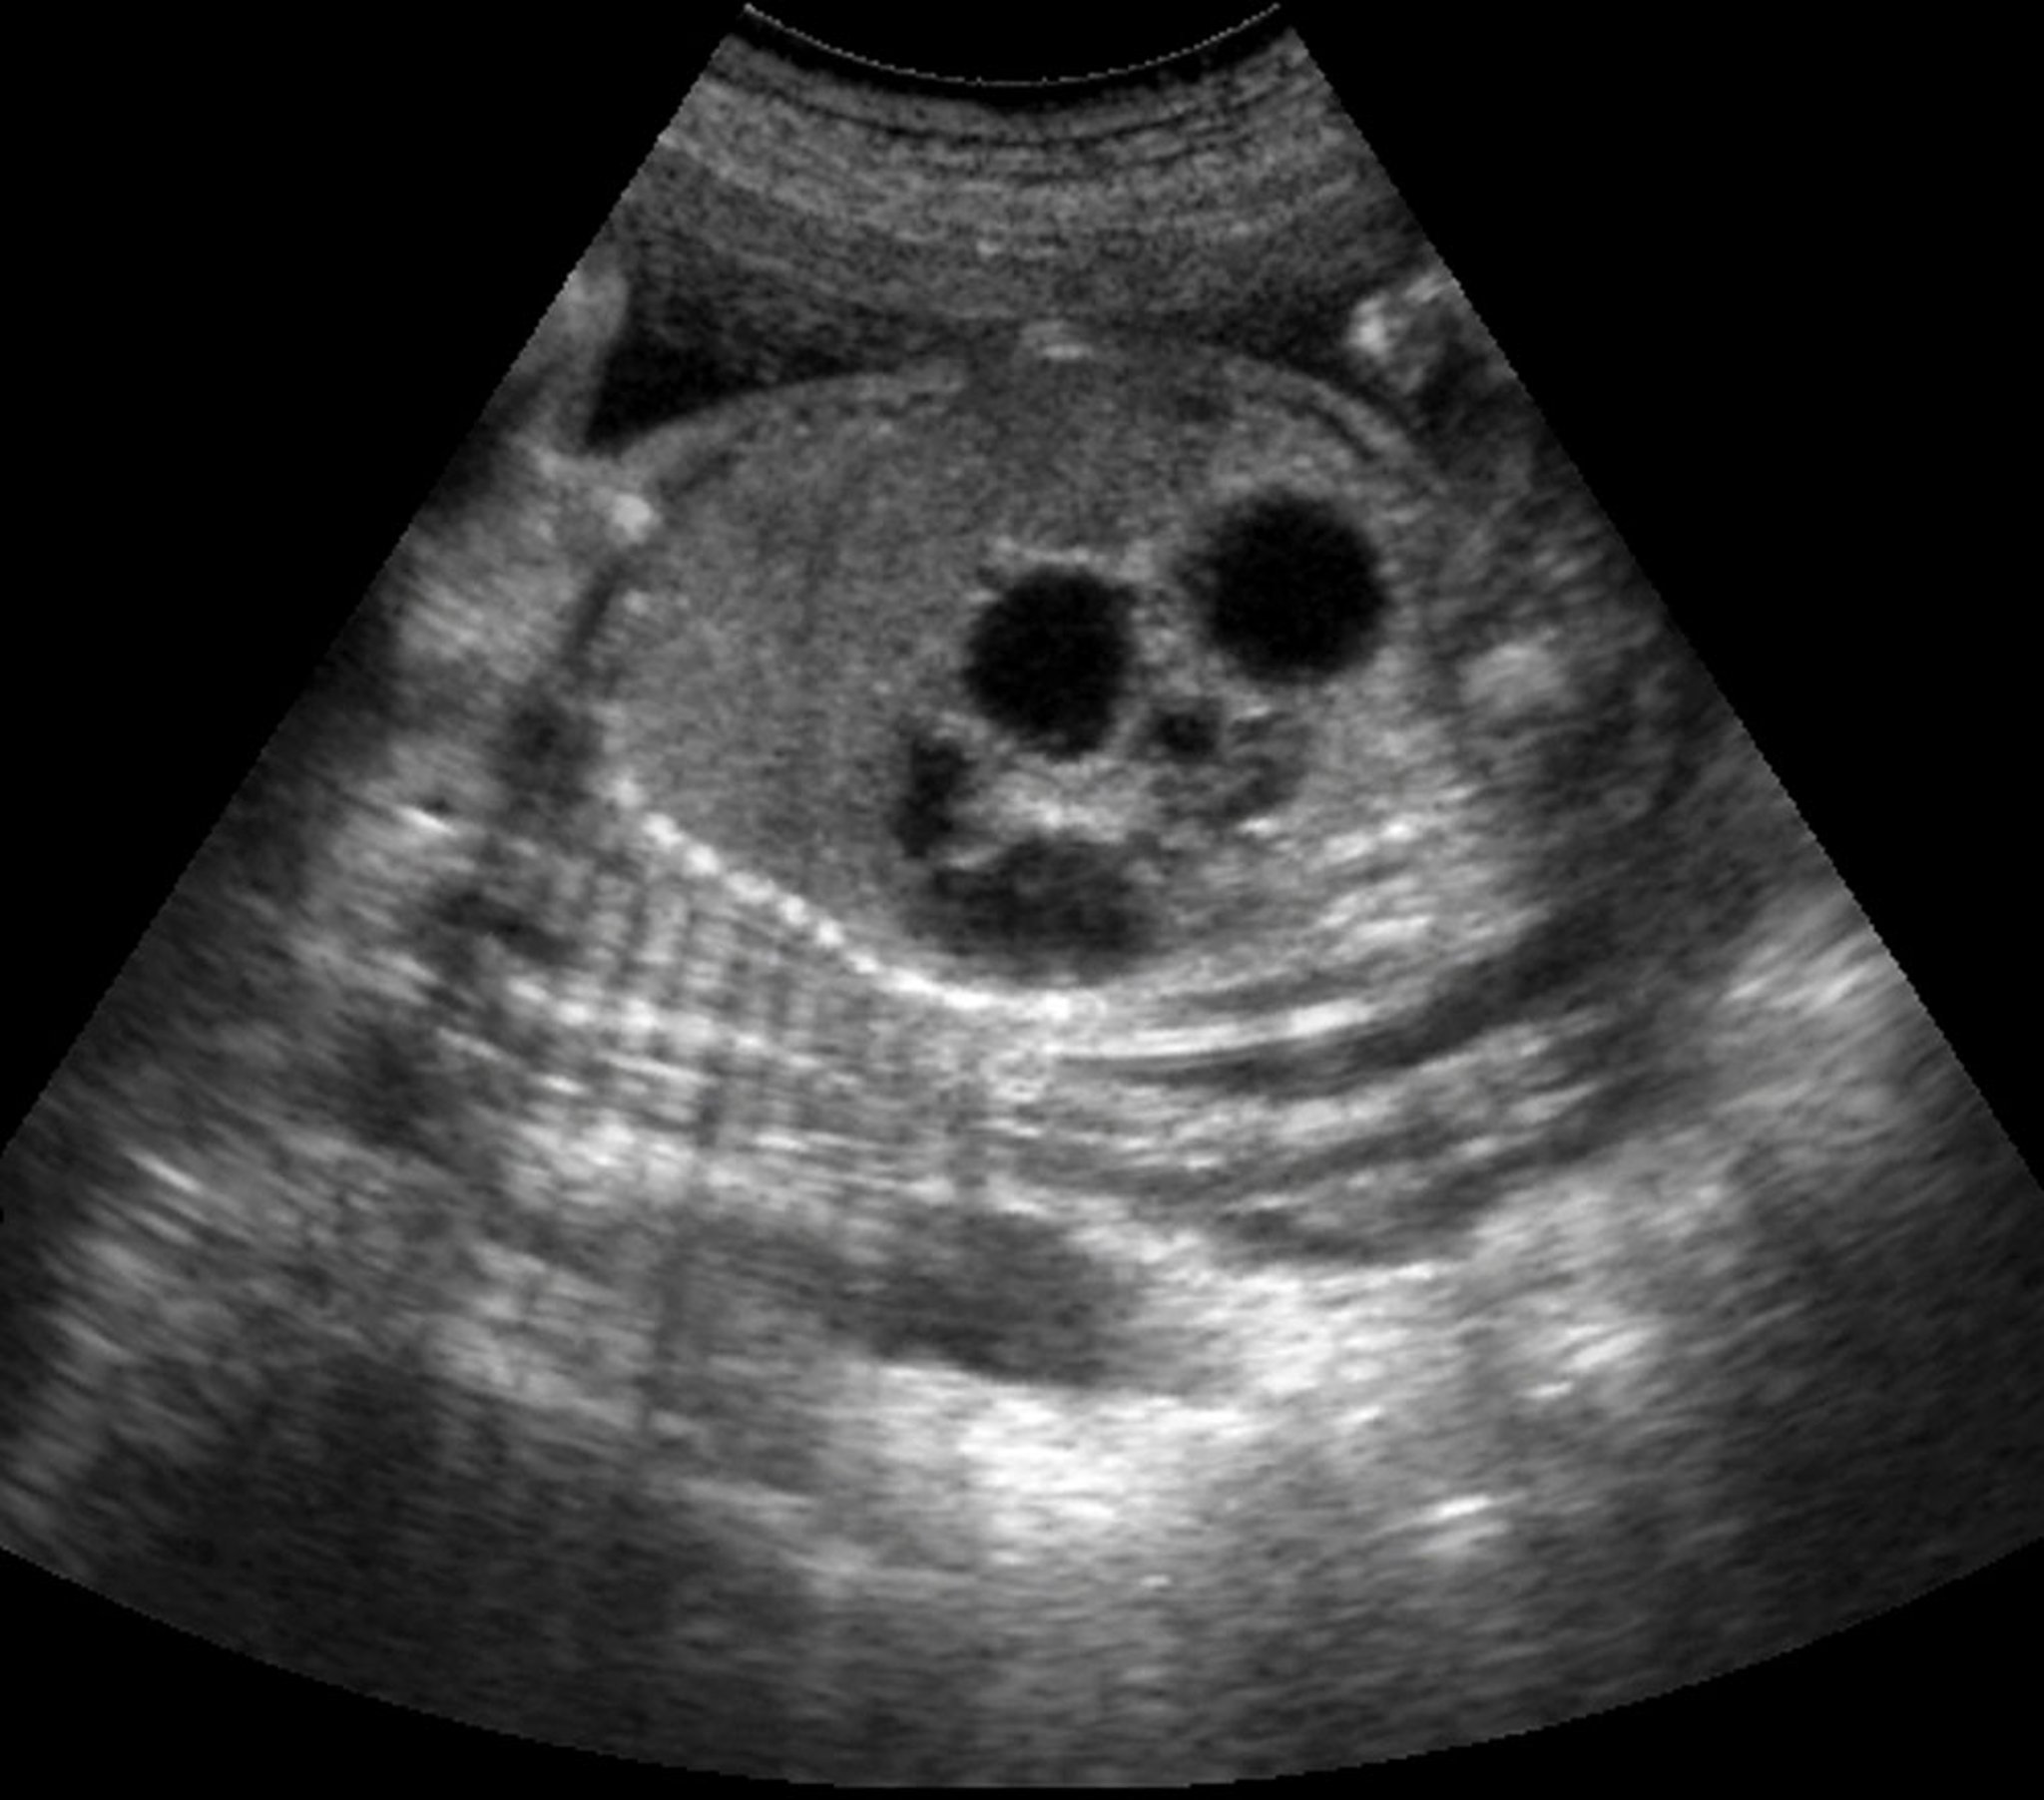

Double-Bubble Effect (Ultrasound)

This ultrasound shows the double-bubble sign in a fetus with duodenal atresia.